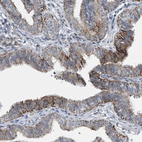

Immunohistochemical staining of human Endometrium shows moderate membranous positivity in glandular cells.